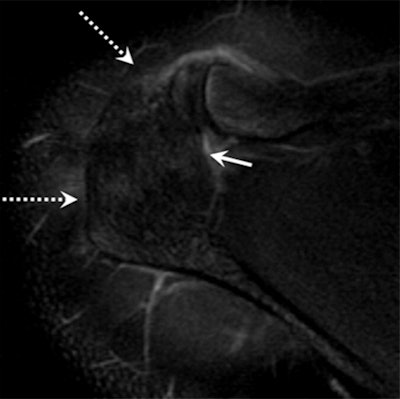

Image above shows incomplete fusion with moderate bone marrow edema in an 18-year-old male pitcher with acromial apophysiolysis. MR image below in the same patient at age 25 after quitting pitching shows complete fusion and resolution of the previously seen acromial edema (dashed arrows). Images courtesy of Radiology.

The researchers found that 25 (86%) of the 29 acromial apophysiolysis patients with follow-up imaging showed os acromiale, or incomplete fusion, compared with just one person (4%) out of 23 in the control group. Meanwhile, 15 (68%) of 22 acromial apophysiolysis patients had rotator cuff tears, compared with six (29%) of 21 control subjects.

The majority of patients who stopped pitching had no long-term adverse effects. However, after a three-month break, 21 of the 29 pitchers with acromial apophysiolysis had continued pitching, and all 21 developed os acromiale.